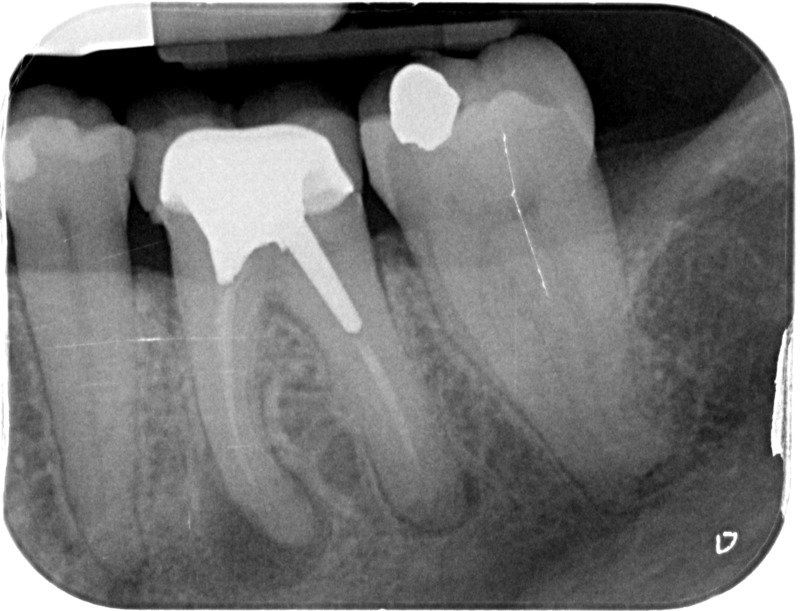

• Apexification : Chez le jeune enfant, une dent immature victime d’un traumatisme ou d’une carie volumineuse peut poser problème. Si la pulpe agressée se nécrose, alors la racine ne s’édifie plus et une lésion inflammatoire se développe au niveau osseux. L’apexification, par apposition d’un matériau biocompatible dans la racine, cherche à induire la formation d’une barrière artificielle à l’extrémité de celle-ci, et permettre la cicatrisation de la lésion dans le but de maintenir la dent en bouche à long terme.

Avant